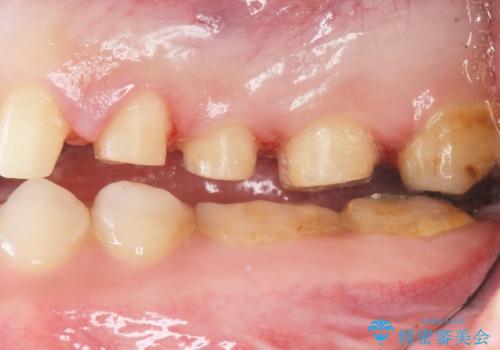

- K-POP(Kポップ)アイドルのような歯にしたいと希望され来院された患者様です。

矯正を途中でやめてしまったとのことで、歯に矯正の接着材が残っており着色も顕著でした。

奥歯の咬合面にはレジンが盛られた状態でした。

見た目と咬み合わせを改善するため、セラミッククラウンによる治療を行いました。